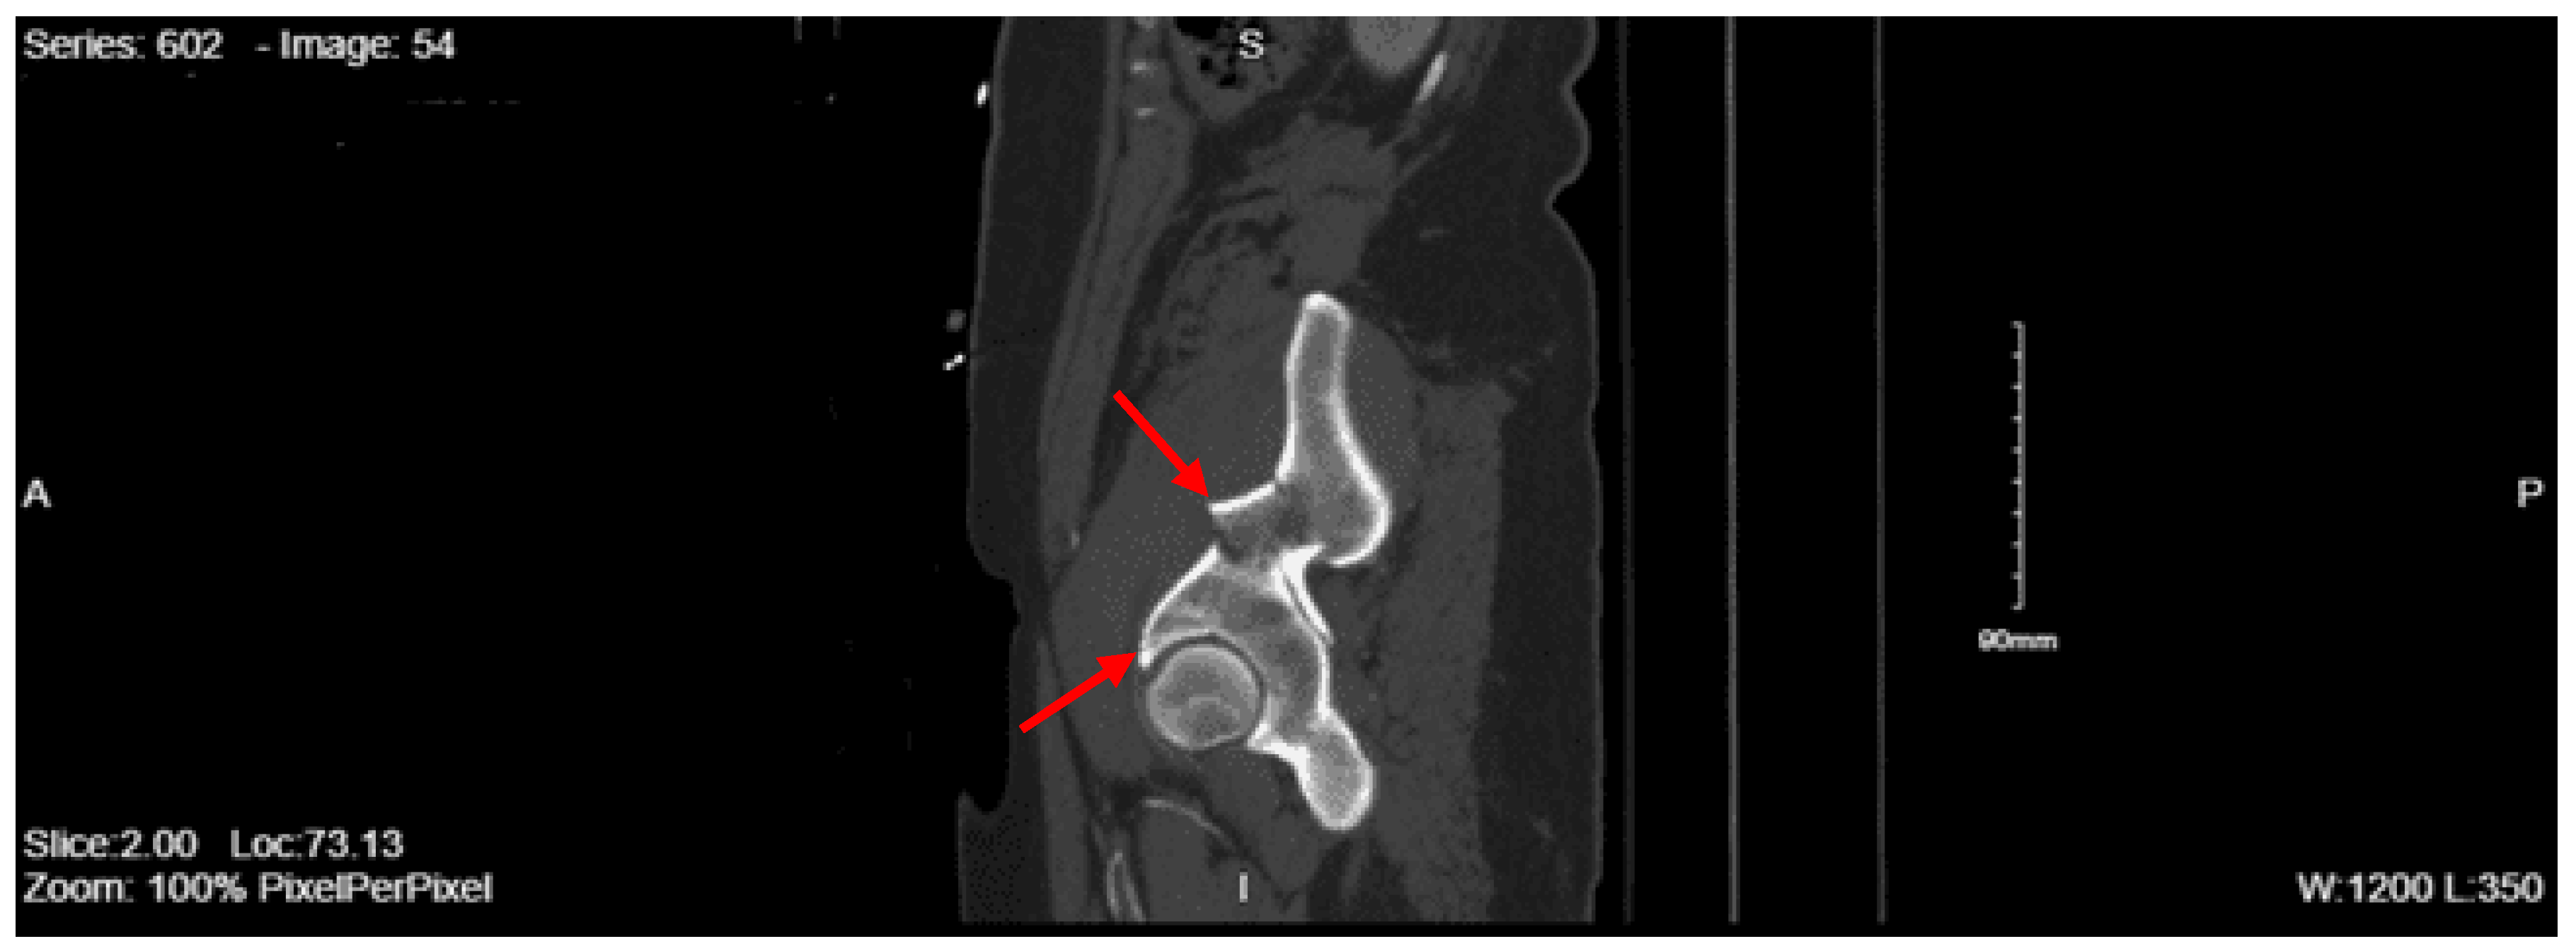

Imaging as shown in Figure 17 and Figure 18:

Portable Chest XR: No acute findings

Portable Pelvis XR: No acute fracture or dislocation, severe right hip osteoarthropathy with extensive bony remodeling of the superolateral femoral head

CT abdomen pelvis with contrast: Acute nondisplaced bilateral sacral alar fractures with extension into the sacroiliac joint on the right and probable involvement of the right S3 neural foramen. Amorphous hematoma in the medial left gluteal musculature and subcutaneous fat measuring approximately 3.3 x 6.6 x 7.7 cm. No visceral organ injury.